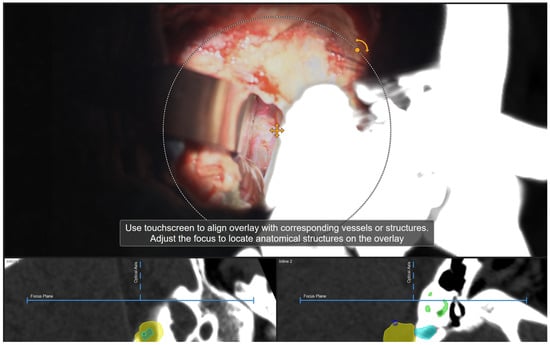

| Patient Number | Segmented Structures in AR Advantages: Craniotomy Planning, Dural Opening, Relations of Tumor to CN V, Localization of Origin of CVI and CVIII at the Brain Stem, Relations of Tumor to Brain Stem, Localization of IV Ventricle, Segmentation of Tumor Cyst, Localization of Structures of the Middle Ear for Facilitation of Drilling on Inner Acoustic Meatus, Relations of Tumor to Arterial Vessels and to Petrosal Vein | ||||||||||

|---|---|---|---|---|---|---|---|---|---|---|---|

| Sigmoid Sinus | Transverse Sinus | Tumor Outline | CN VII and VII Origin at Brain Stem | CN V | Petrous Vein | Arterial Vessels (AICA, PICA, SCA) | Brain Stem | Middle Ear, Cochlea and Semicircular Canals | Pyramidal Tract | IV Ventricle | |